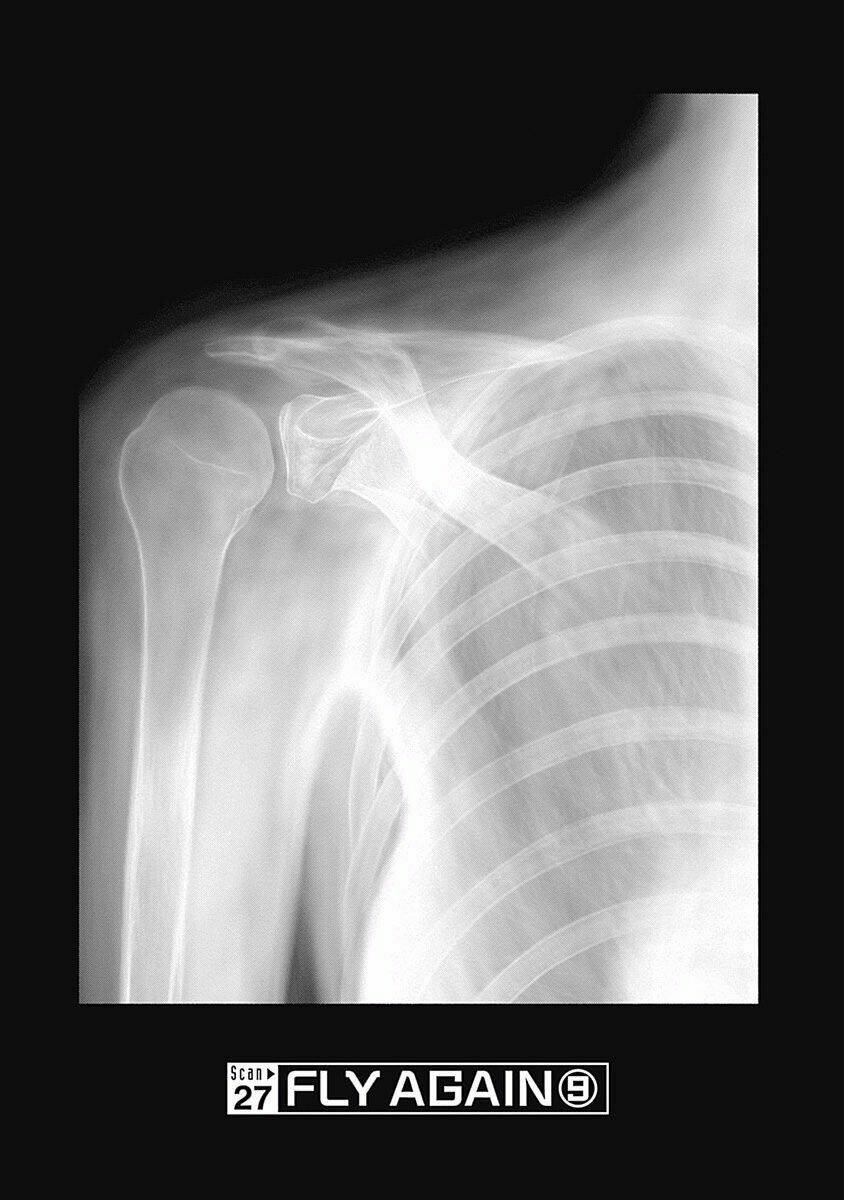

Radiation House

— chap 27